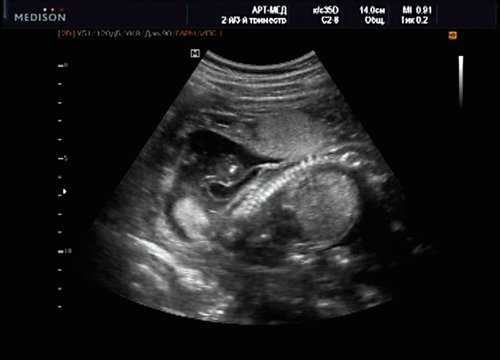

Клиническое наблюдение 4

Беременная 25 лет, обратилась в клинику в срок 18 нед. При эхографии выявлена грубая кифотическая деформация позвоночника в поясничном отделе (рис. 19).

Рис. 19. Деформация позвоночника.

В проекции деформации определяется миеломенингоцеле (рис. 20).

Рис. 20. Миеломенингоцеле.

Обнаружение типичных эхографических признаков позволило установить диагноз миеломенингоцеле.